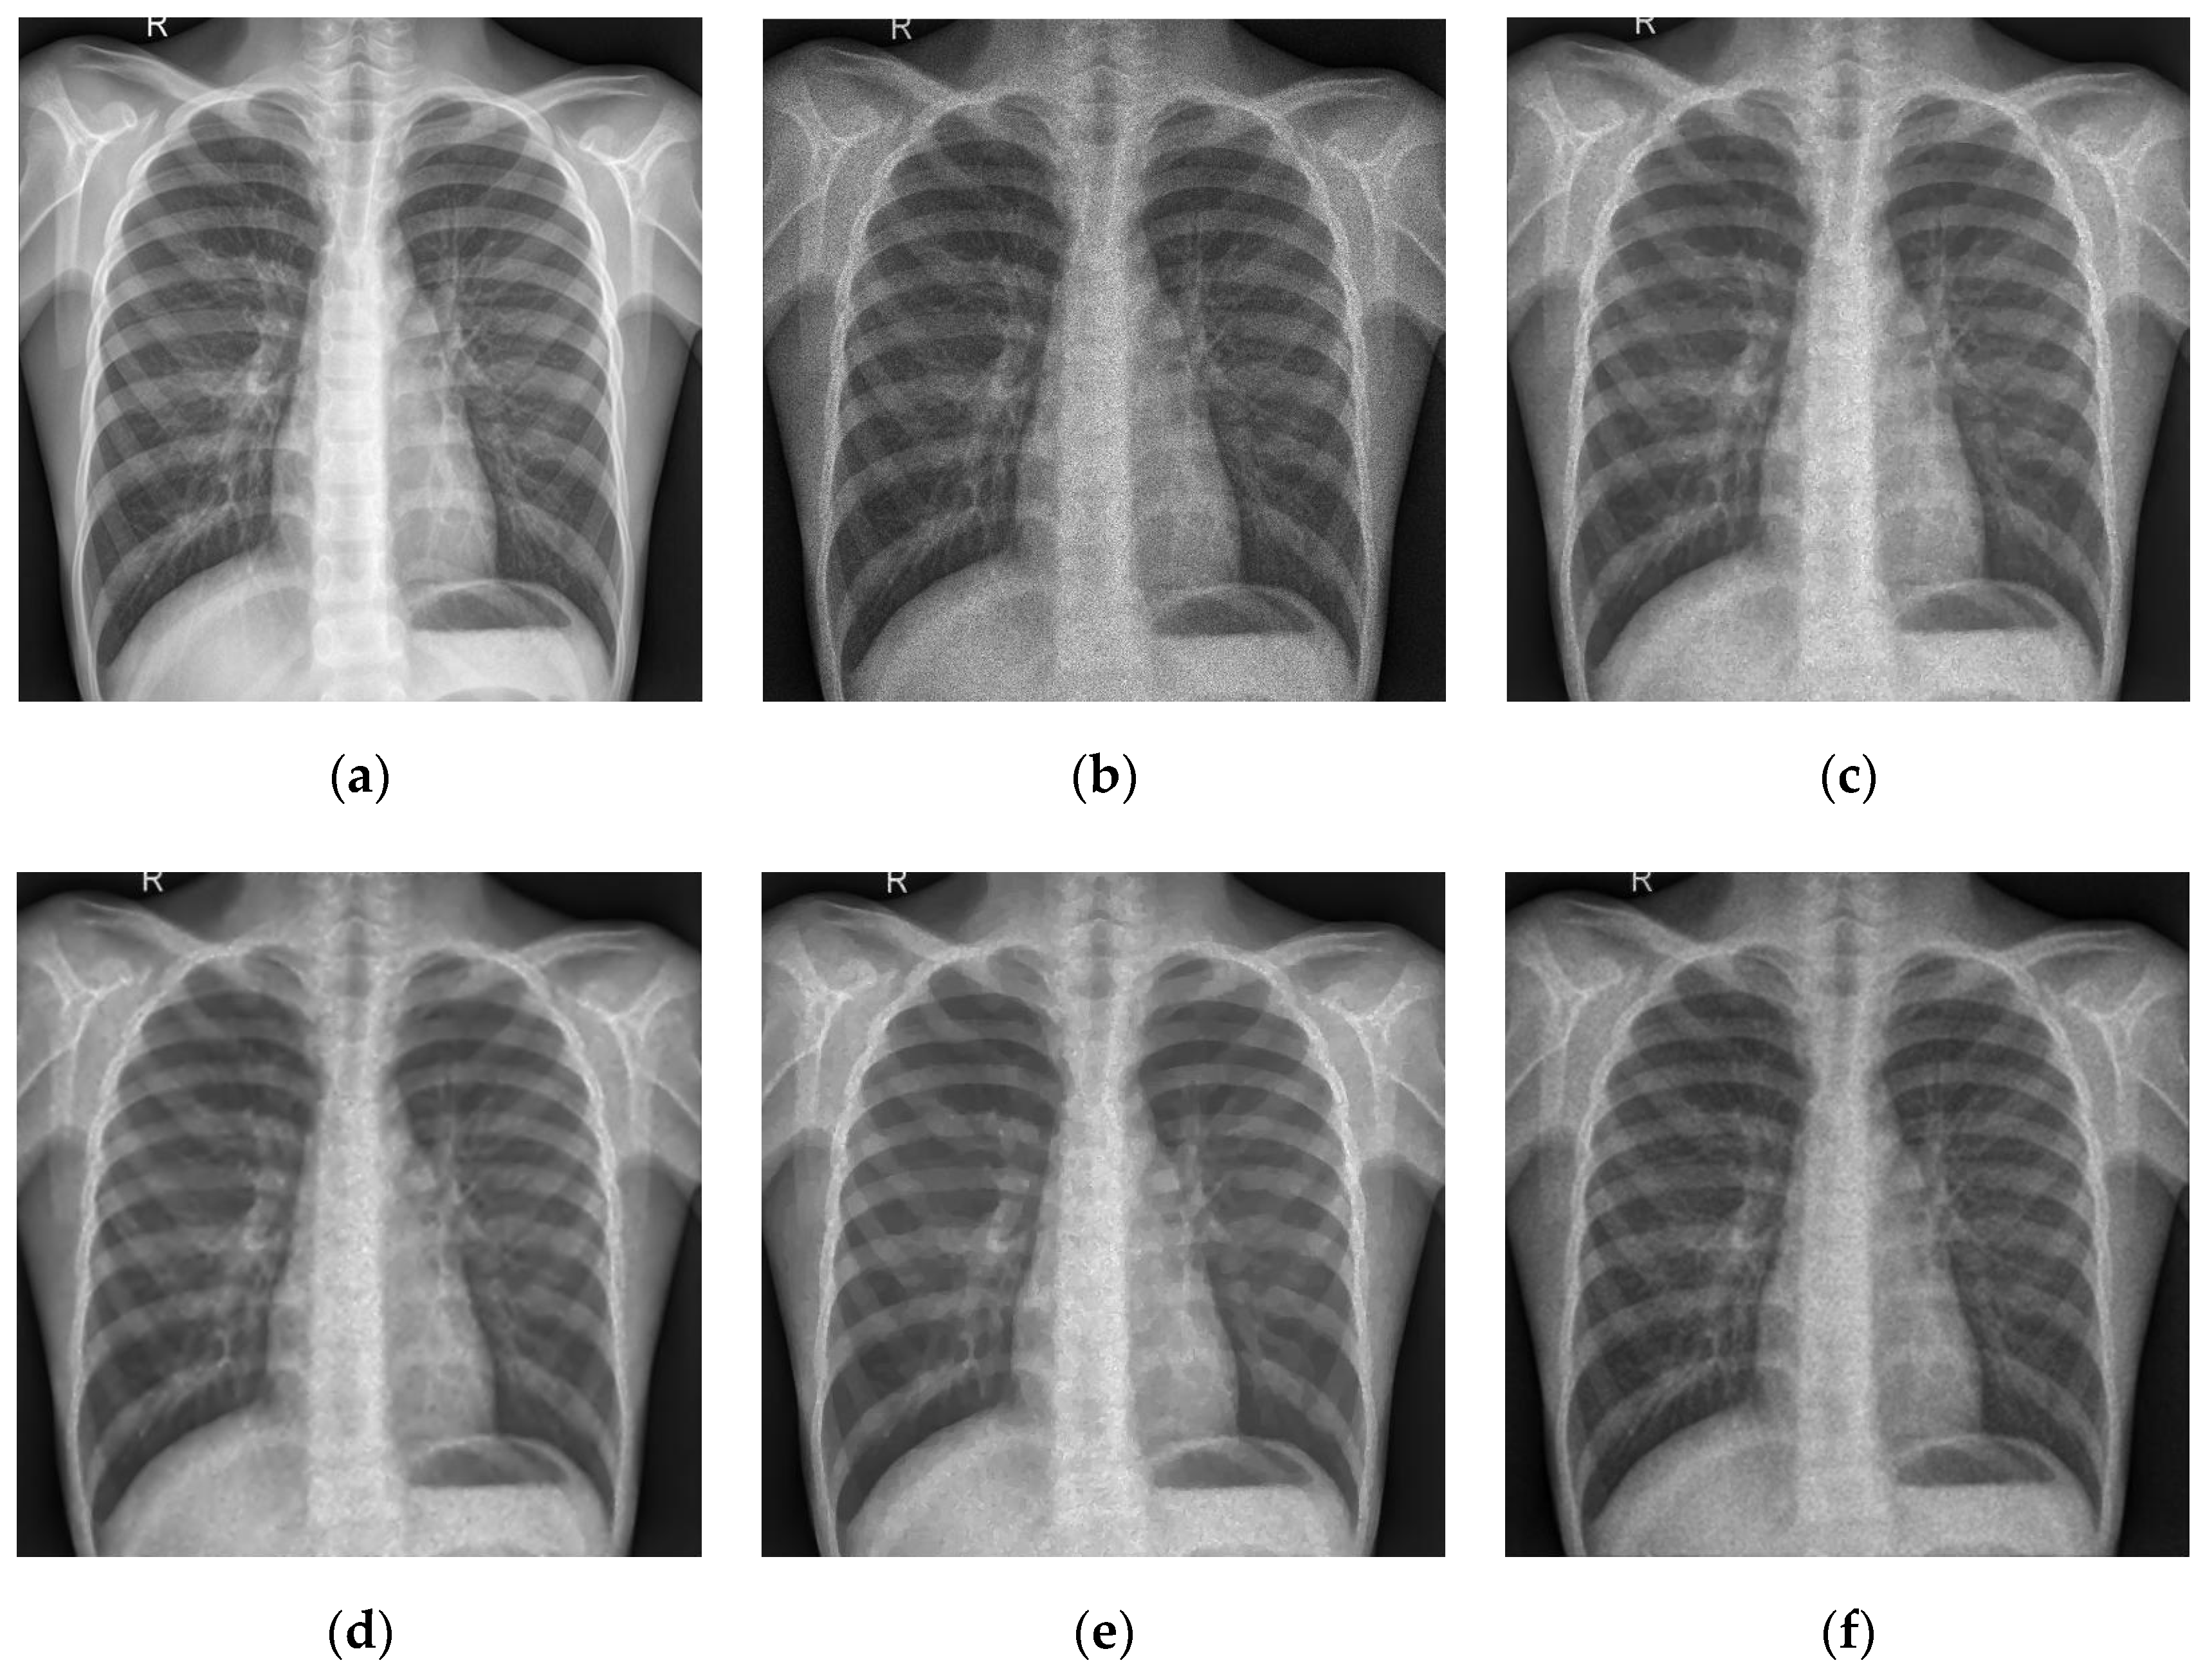

5.2. Numerical Simulations on Medical Images

5.2.2. Different Methods

- Partial Differential Equation Method

- ADMM Method

5.2.3. Comparison with Other Variational Models